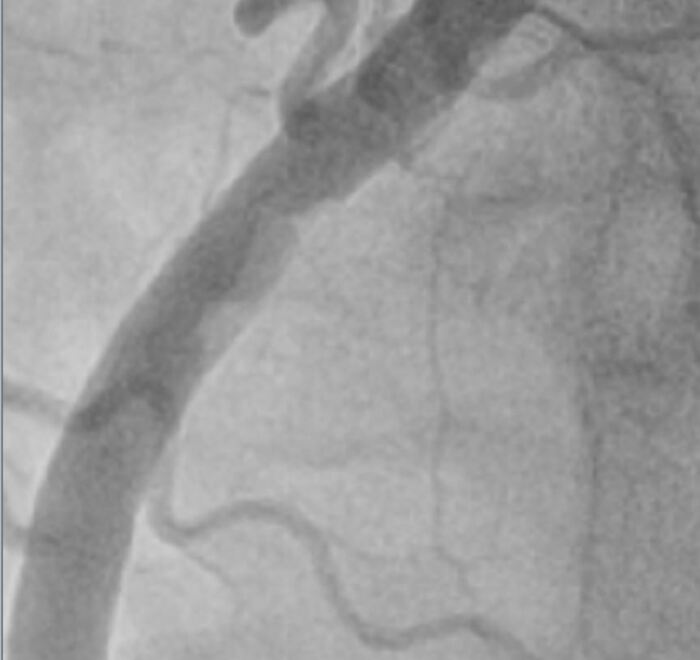

Более крупно место где все началось:

Красным зона пристеночного тромбоза, он неоднороден по плотности, рыхлый и отсюда мигрировали тромбы вниз, закупорив дистальные ветви -> как итог инфаркт.